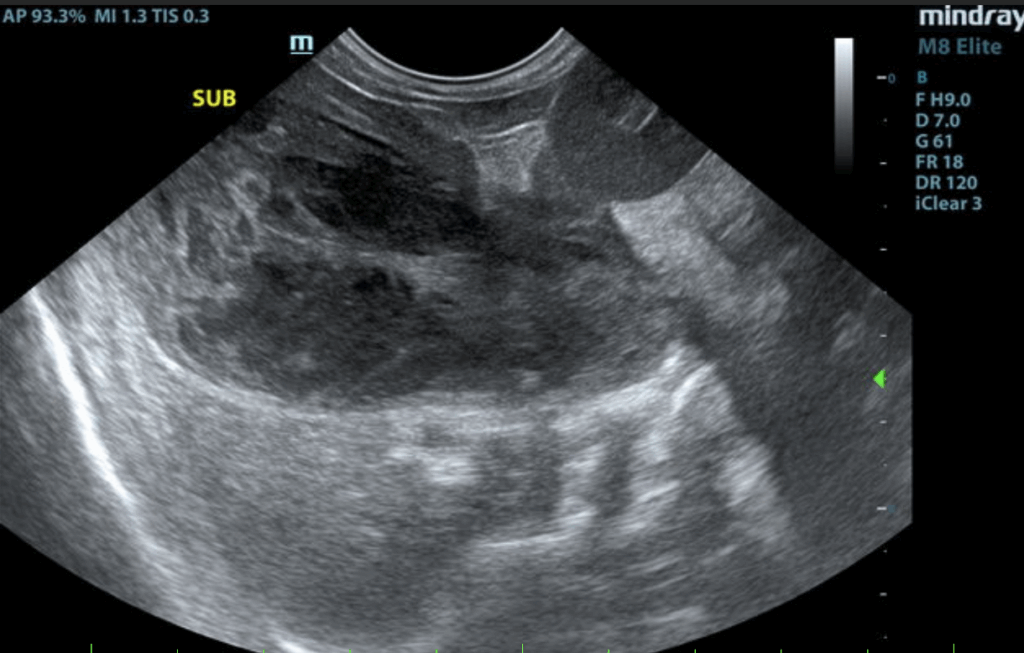

The liver presented enlarged in size. The parenchyma of the liver was subjectively normal in echogenicity compared to the spleen and renal cortices. The liver parenchyma was uniform with a mildly coarse echotexture. The capsule of the liver was symmetrically rounded to mildly swollen in margination. A solitary, small ventrocaudal thinly walled intraparenchymal cyst was present. The hepatic and portal vasculature were normal in appearance without signs of congestion. The gallbladder was distended in size with echogenic thickening of the gallbladder wall. There was biliary sludge that appeared to be non-mobile and organized. A stellate pattern to the organized biliary sludge was present. Regional pericholecystic omental inflammation without overt effusion was present. The common bile duct was not visualized.

• Gallbladder mucocele with peripheral inflammation.

Given gallbladder mucocele with pericholecystic inflammation and concurrent hepatopathy, cholecystectomy with hepatic biopsies assuming normal clotting status is warranted. However, given clinical history in this patient, surgical considerations may be limited. Likewise, even with surgery, overall prognosis is considered guarded given the possibility of mild bile leakage or possible emerging bile peritonitis. Gallbladder mucocele may be associated with Cushing’s syndrome or hypothyroidism. Hepato-gastrointestinal support would be reasonable. If surgery is elected in this patient, recheck echocardiogram indicated to assess anesthetic risk.

Abdominal ultrasound is diagnostic for a gallbladder mucocele. A gallbladder mucocele typically has a striated, stellate appearance and the material is not mobile. Common findings on ultrasound include a thickened gallbladder wall, free fluid and increased echogenicity of surrounding tissue in the gallbladder fossa. Gallbladder rupture is diagnosed on ultrasound by a discontinuity of the gallbladder wall, hyperechogenicity of the cranial abdominal fat, free peritoneal fluid, or a free, well-organised mucocoele within the peritoneal cavity.